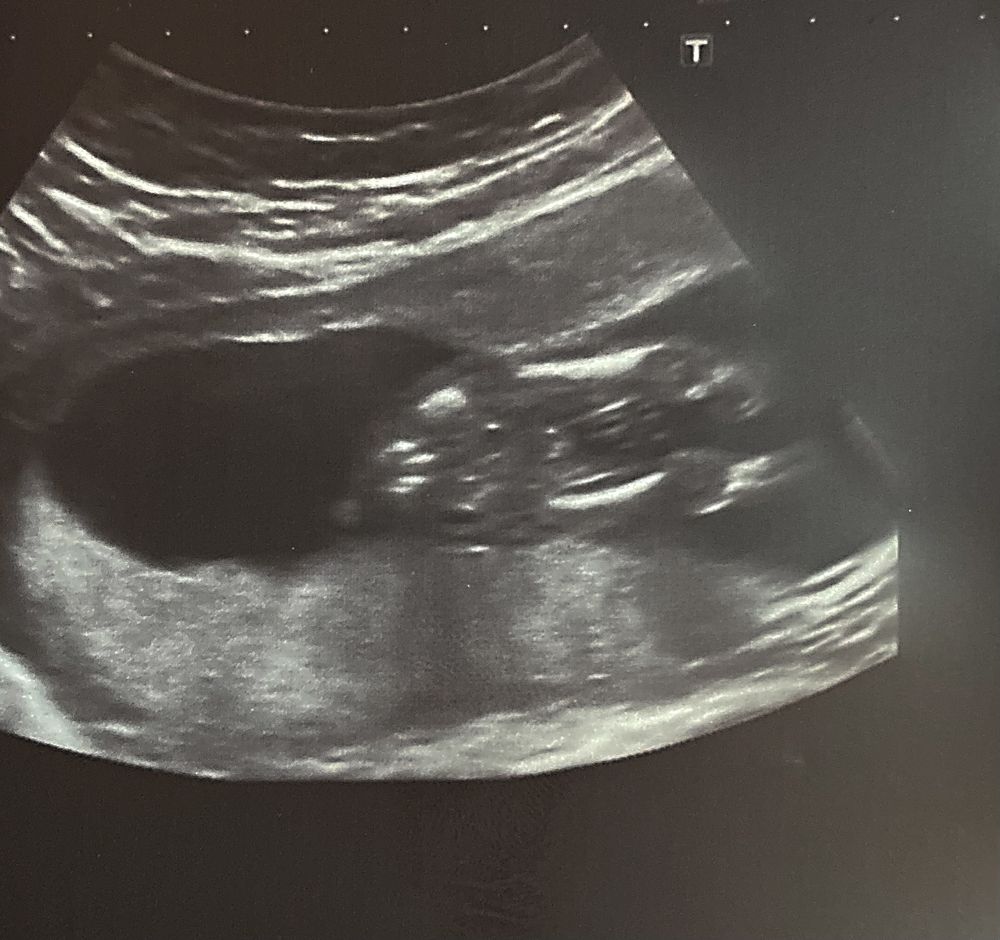

Узи на 15 акушерской неделе

Тоже делала УЗИ в 15 недель ровно, похожая картинка) и тоже сказали - 80% мальчик Изображение

Врач на узи сказала что не 100% мальчик сказала проверить на 2 скрининге там точно скажут

Норм не стеснительный пацан) поздравляю

Даа мальчик ))) не стеснительный)))

Да уж! Все показал! 😂 поздравляю вас!